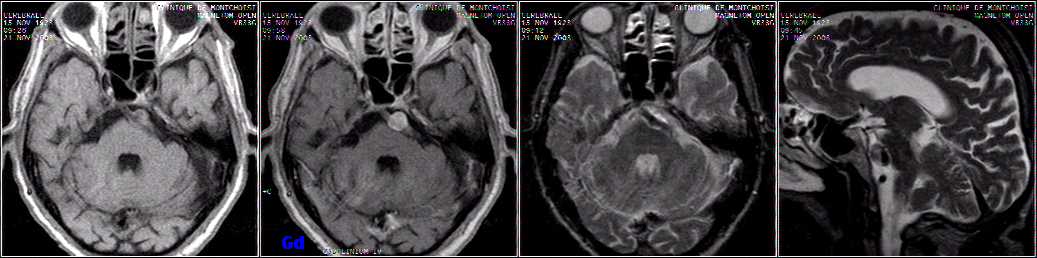

Brain sag. FLAIR, cor. T1 Gd,

axial T1 Gd & T2: cerebellum hemangioblastoma.